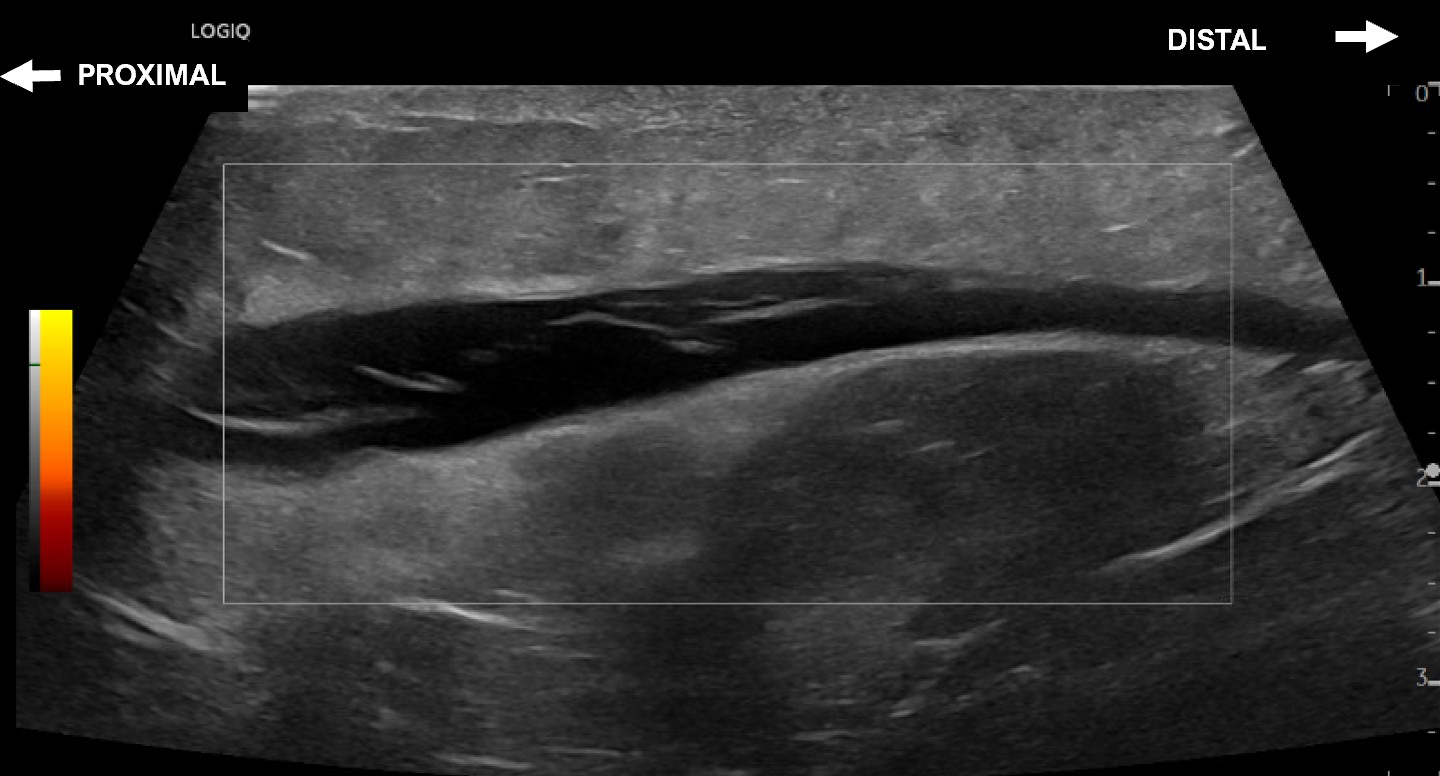

Unlabeled long axis view of a Morel-Lavallee lesion measuring with no evidence of flow on power doppler.